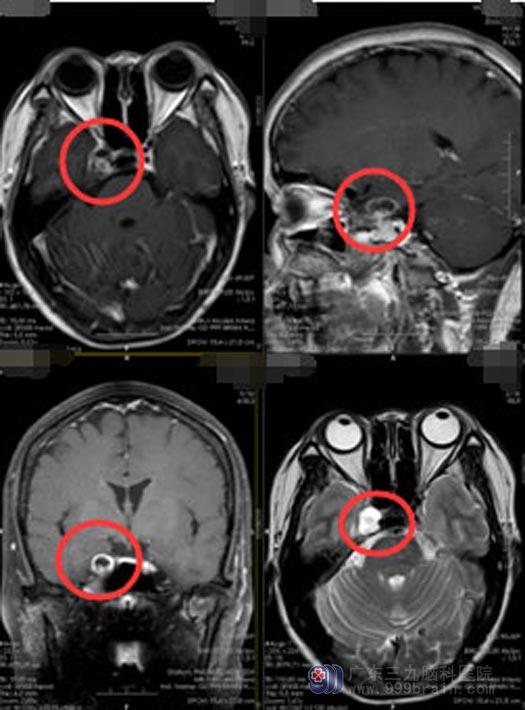

直到3月初,“重影”症状一天比一天严重,才在家人的陪同下,到当地三甲医院就诊,头部MRI检查发现:右侧海绵窦区占位性病变,医生还告诉她:海绵窦区位置深,重要结构多,手术风险很大。

经过同乡的推荐,他们来到了广东三九脑科医院神经外五科。进一步头颅MRI检查发现:右侧鞍旁-蝶骨占位性病变,部分向为颅外生长,神经鞘瘤可能。